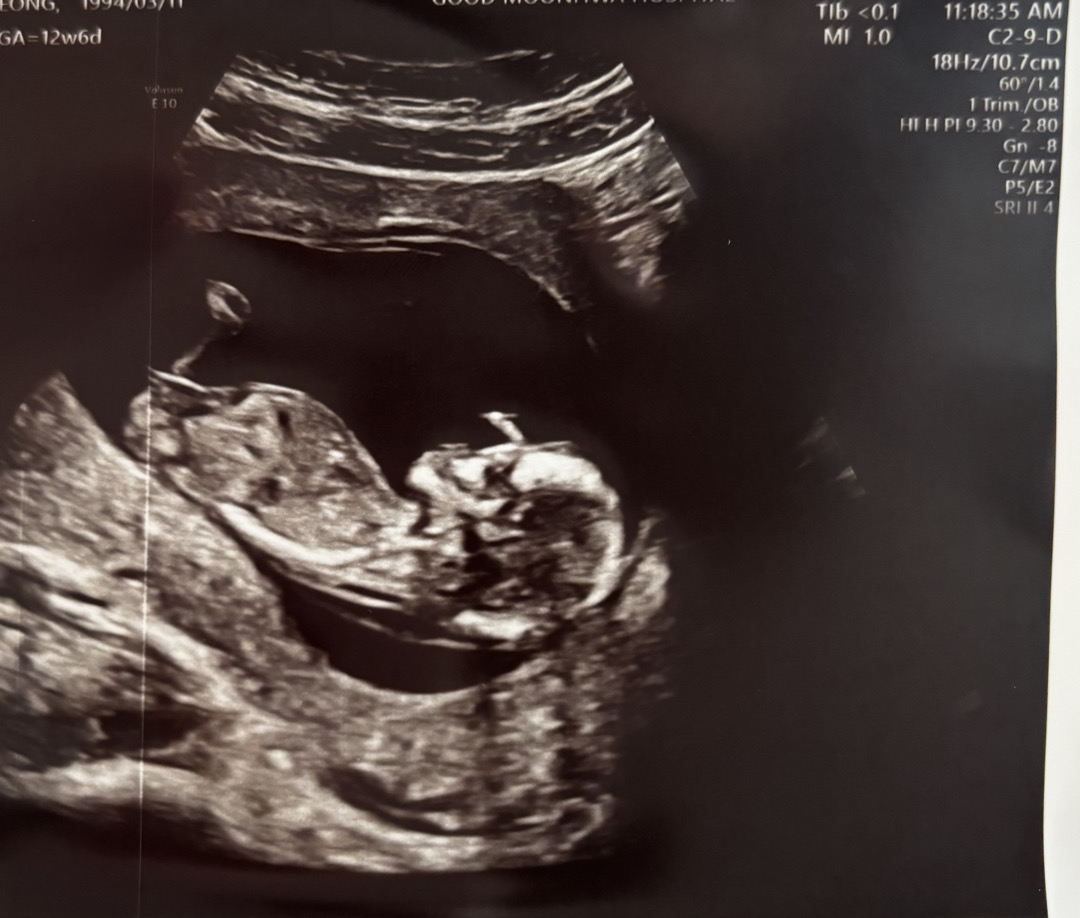

12주 6일차 성별 예측 도와주세요/딸

아들같은 딸이면 좋겠어요ㅎㅎ 물구나무 서있어서 선생님이 한참 배를 흔드시고 겨우 찍었어요! 성별 예측 도와주세용 ————- 딸이래용 감사합니다❤️